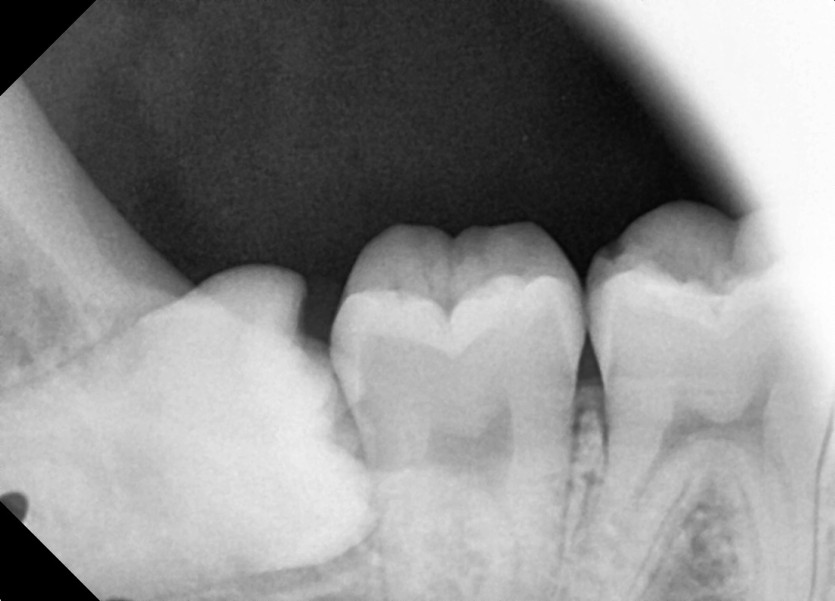

#18,48 사랑니 발치

구강 외과 전문의가 당일 발치했습니다.